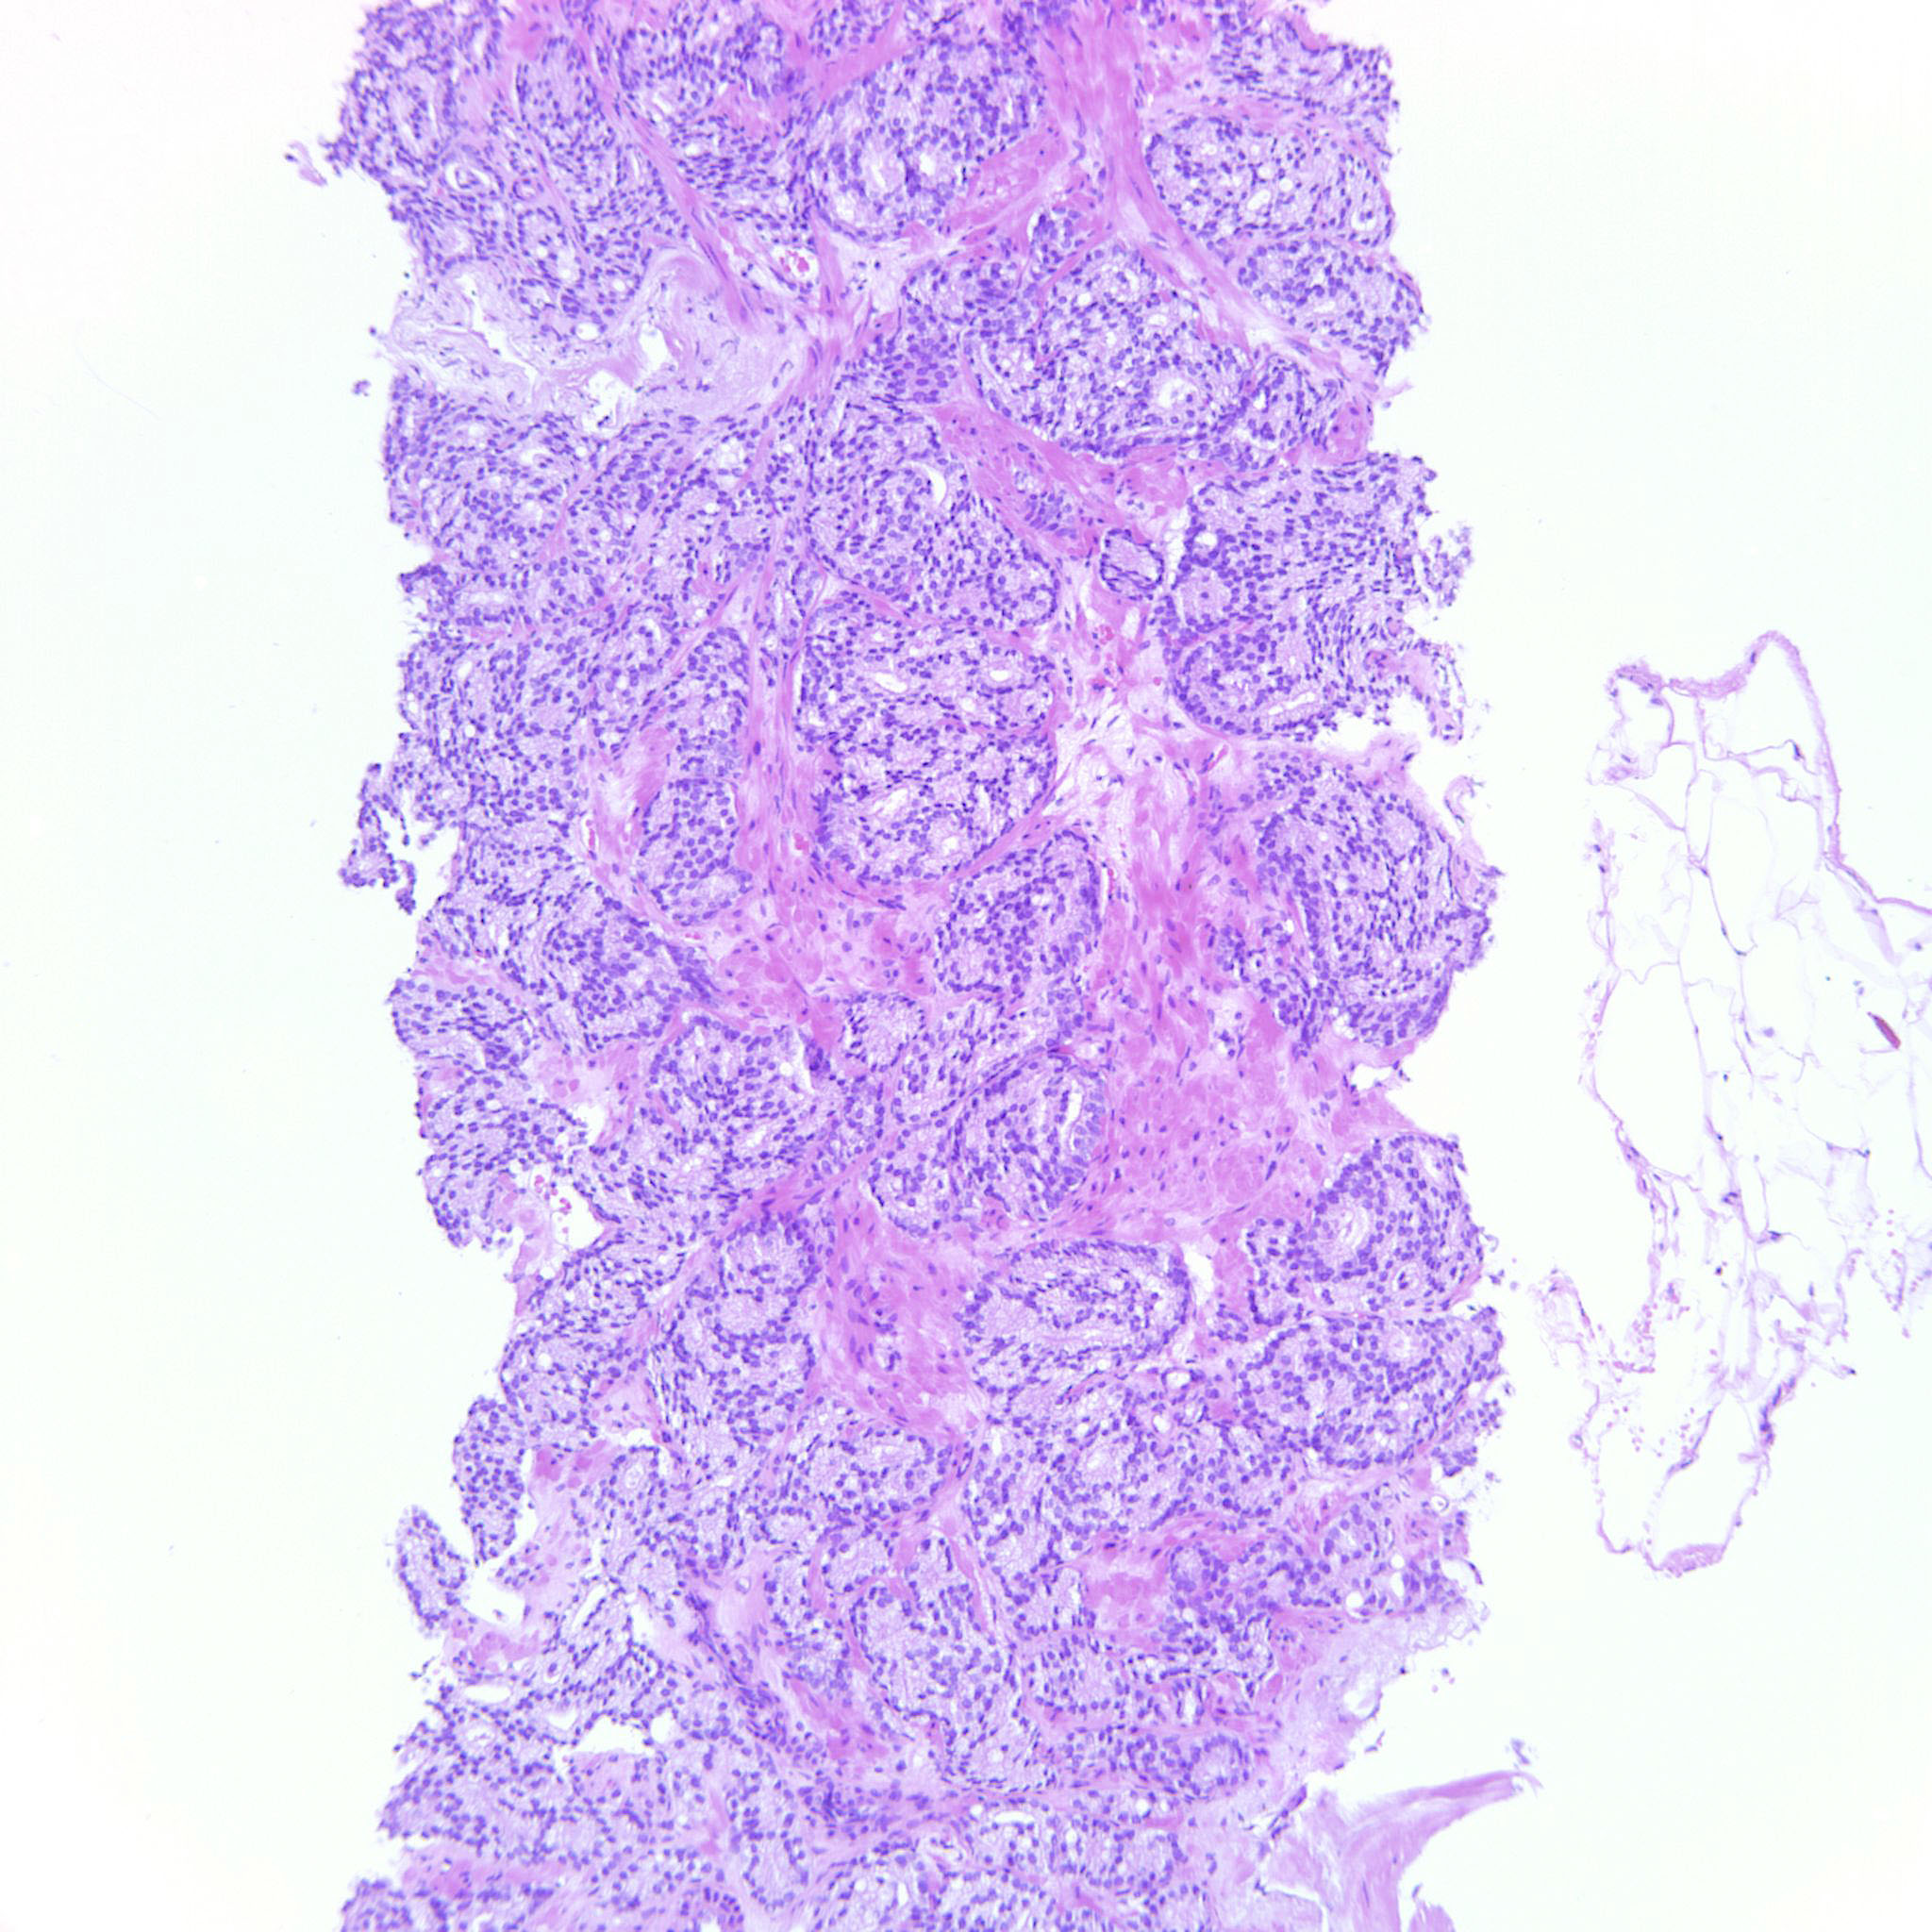

Prostate cancer grading

Case ID: 122